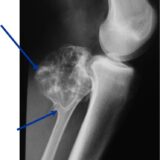

Author معمل جرين Tags اسباب هشاشه العظام, التحاليل, التحاليل الطبيه, امراض العظام, جرينى, معمل جرين, هشاشه العظام

“هشاشة العظام.. العدو الصامت اللي ممكن يكسرك من غير خَبطة!

🦴 إيه هي هشاشة العظام؟ هشاشة العظام هي مرض بيخلي العضم يفقد كثافته وقو...